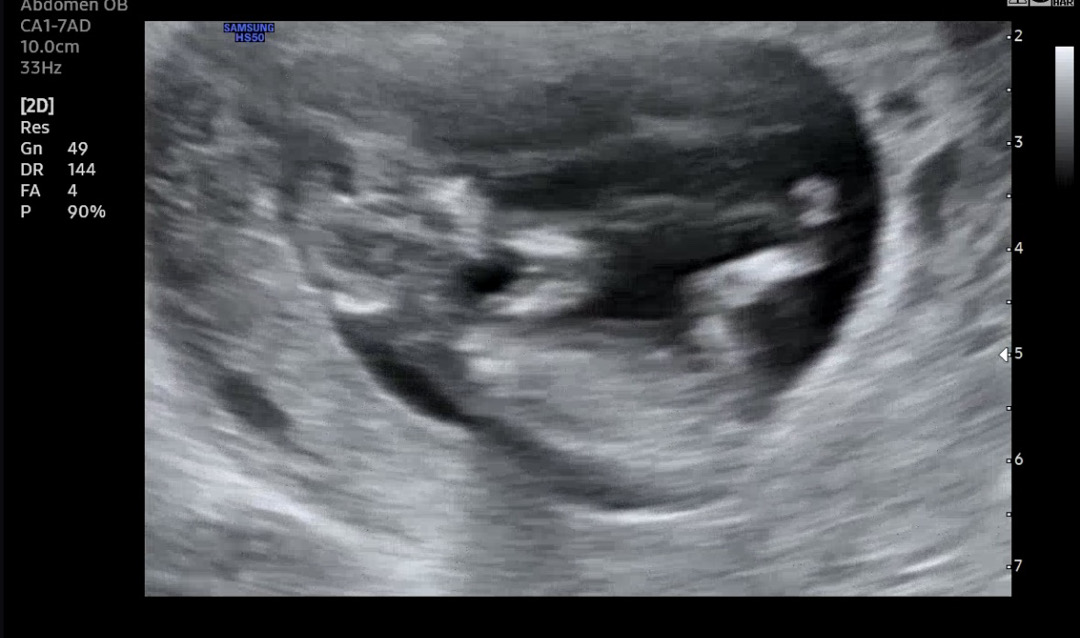

저도 각도법궁금해요!!

선생님이 딸일 가능성이 더 높을것같다 하긴하셨어옹 ㅠㅠ 전 아들을 바라고 있어서요! 딸이든아들이든 다 좋지만 ㅎㅎ 무튼 각도법 잘보시는 분들 의견도 궁금해요

딸같아요

역시 딸인것인가..!.!!